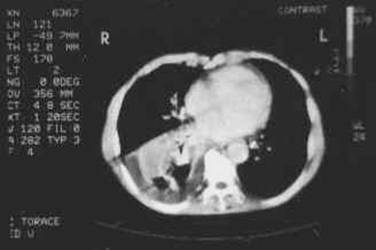

Femeie de 70 ani. Disfonie progresiva prin

paralizie de recurent drept. Nodul voluminos (35 x 25 x 43 mm, 19 cc) care ocupa

aproape complet lobul drept, neomogen, hipoecogen, cu arie anterioara

hipoecogena. Lob stang nevizuzlizat (probabil agenezie). Calcitonina =

820 pg/ml. (v.n. <10pg)

CEA= 638 ng/ml (v.n. <8 ng).

Examen citologic prin citoaspiratie: carcinom midolar cu celule spindle.

CT – aceeasi pacienta – agenezie lob stang